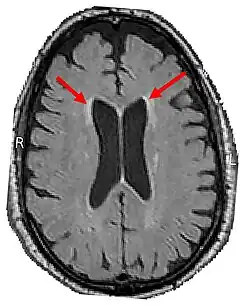

Brain CT of brain showing white matter lesions (indicated by the red arrows)

Core Features

4. Brain CT/MRI findings:

1. Bilateral Cerebral white matter lesions[11]

2. Thinning of the Corpus Callosum[11]